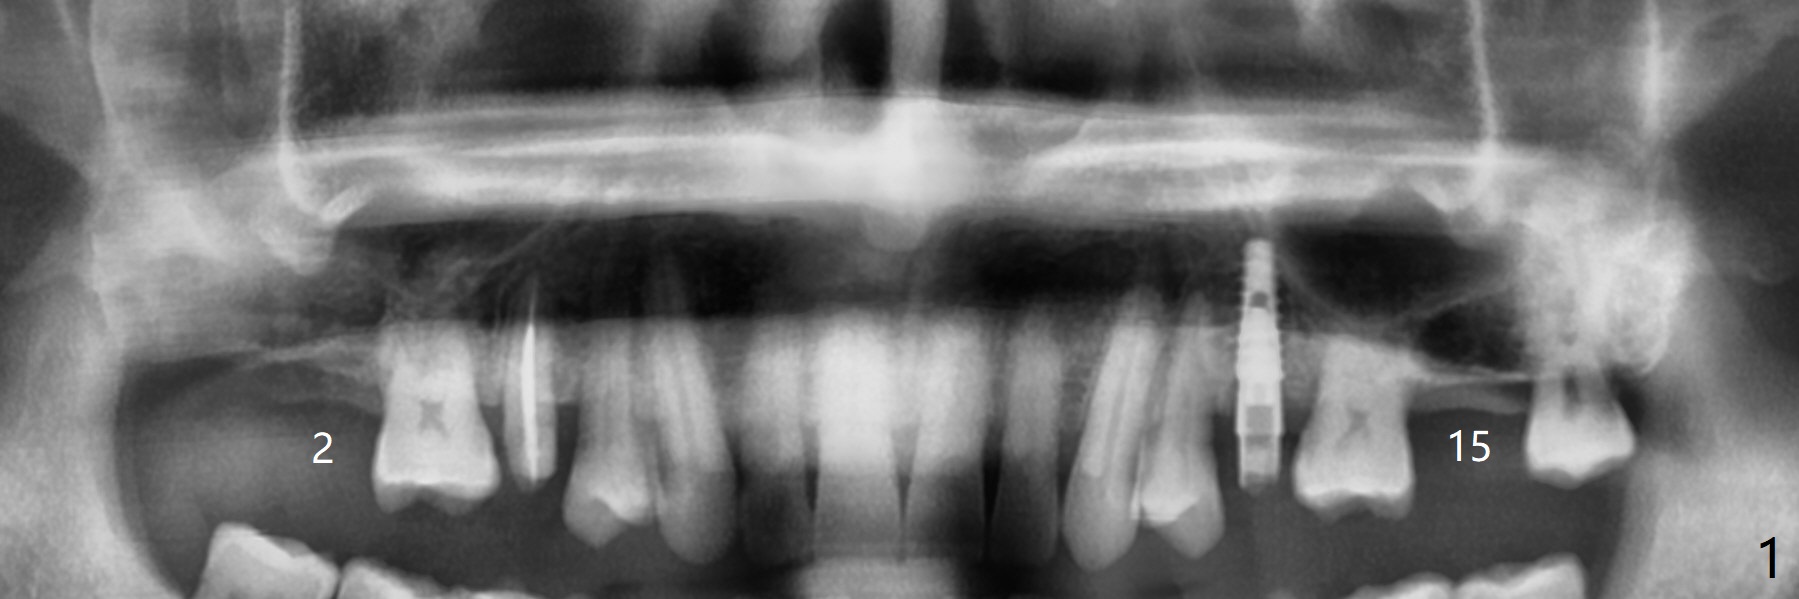

2号牙位点保存后6个月,而15号牙拔除没有植骨1-2年前(图一)。2号牙位骨质高度足够,准备不做上颌窦提升(图二),而15号牙位需要提升(图三,六)。种植术后5个月两个植体愈合均正常(图十一,十二)。